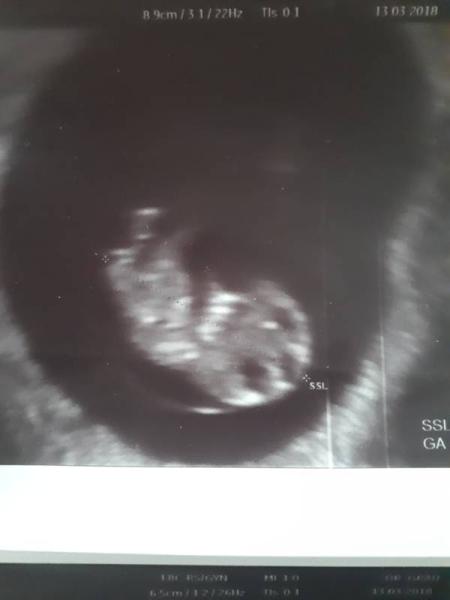

Hallo zusammen, Ich bin heute 10+5 und eigentlich läuft alles gut. Außer, dass ich nach 3 FG super ängstlich bin, aber je näher die 12 Woche kommt umso besser wird es. Jetzt hab ich heute wieder ein bisschen rumgelesen und bin zufällig auf Ultraschallbilder gestoßen, die eine verdickte Nackenfalte gezeigt haben. Bei einem BIld dachte ich mir noch: das kommt mir bekannt vor und hab meinen Mutterpass rausgezogen und das Bild von 9+2 angeschaut. Und man sieht genau am Kopf beginnen so einen runden Kreis, der am Rücken entlang läuft. Jetzt hat mich natürlich wieder die Angst gepackt :-( Jetzt hab ich natürlich Angst, dass man da schon eeine massiv verdickte Nackenfalte sieht. Mein Arzt hat damals nichts dazu gesagt und ich war diese Woche auch nochmal dort und auch da hat er nichts gesagt. Leider bin ich mir nicht so sicher, ob er es mir gleich sagen würde, da er meine Ängste kennt. Die Bilder von dieser Woche sind leider nicht seitlich, daher kann ich da nicht nochmal schauen. Außerdem hab ich auch gesehen, dass er bei der ersten Ultraschalluntersuchung bei 9+2 bei Auffälligkeiten den Mutterpass leer gelassen hat. Das verunsichert mich natürlich noch zusätzlich. Vielleicht mag jemand ja mein Bild mal angucken. Danke!

Bild zu Angst nach Ultraschall - Schwanger - wer noch? Rund um die Schwangerschaft

Huhu! Google mal Eihaut. Dann wirst du wissen,was du da bei deinem Baby auf dem Bild siehst Schaut alles super aus! Eine verdickte Nackenfalte schließt ja beim Baby wieder unten an und sieht anders aus...

Das ist die Fruchtblase Ich selbst erlitt zwei FGs. Aber je ruhiger ichbwar, desto gut verläuft die SS. Bin jetzt ende 5. Monat. Alles super. Lass das Googlen und die Vergleiche! Das schürft nur mehr Ängste! Vertraue dir, deinem Körper, deinem Kind, der Natur! VG Wunderbar 2018

Jap das ist die Eihaut und nicht der Nacken ;)